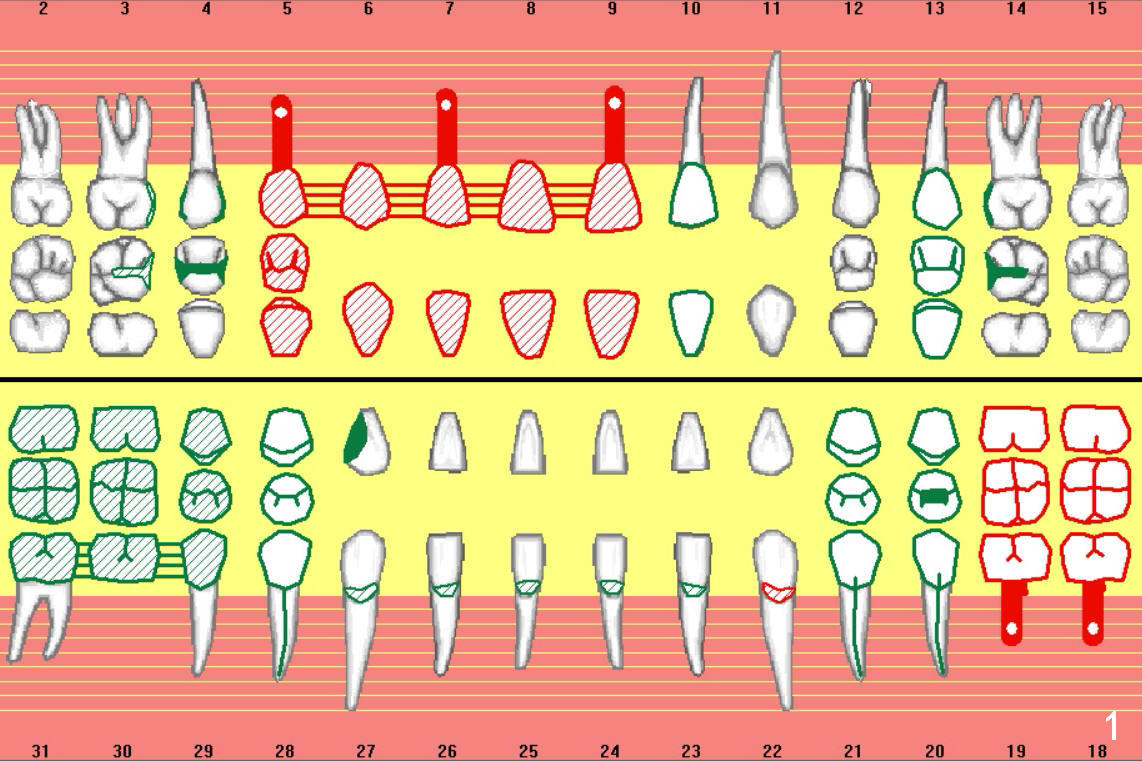

A 69-year-old man would consider implant option for his upper front teeth (Fig.1: #5-9) if there is no separate bone graft procedure. He does not want implants for his lower left molars (#18,19), since he has had a partial denture. In fact the bone at #5-9 is so thin that 2-3 mm 1-piece implants can be placed at #5,7 and 9 (Fig.2-5 (CT coronal sections (B: buccal)) for a 5-unit bridge (Fig.1). To support and increase the longevity of the latter, implants at #18,19 are mandatory (Fig.6,7).

Wheel saws will be used to split the ridge before drilling at #7 (Fig.4). Surgical bur is to be used for ridge reduction prior to osteotomy at #19 (Fig.6), while at #18, osteotomy depth will be 10 mm for 8 mm implant (Fig.7).